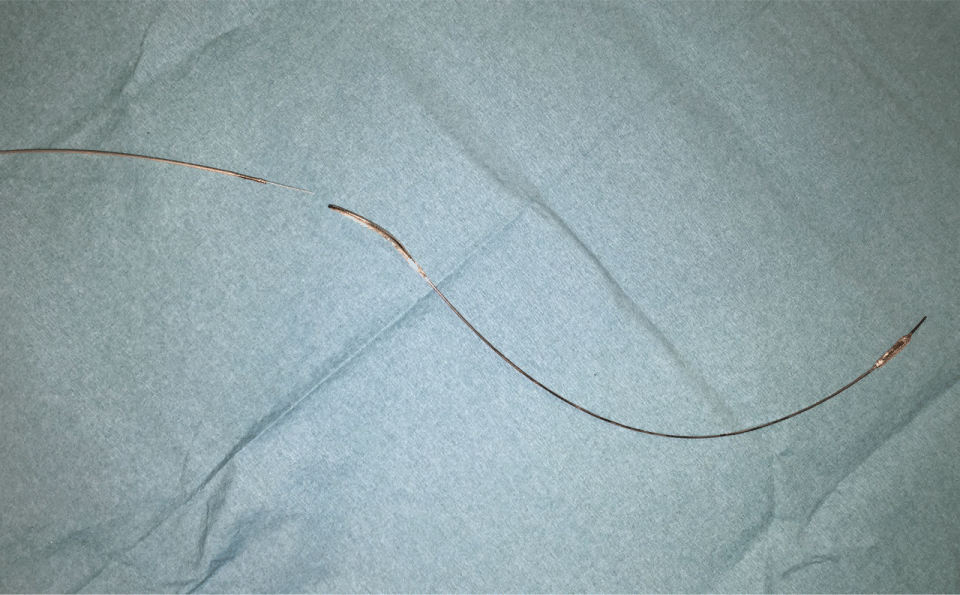

Figure 4: Ruptured balloon after successful removal. View Figure4

Figure 5: Closeup of the site of rupture and detachment. View Figure 5